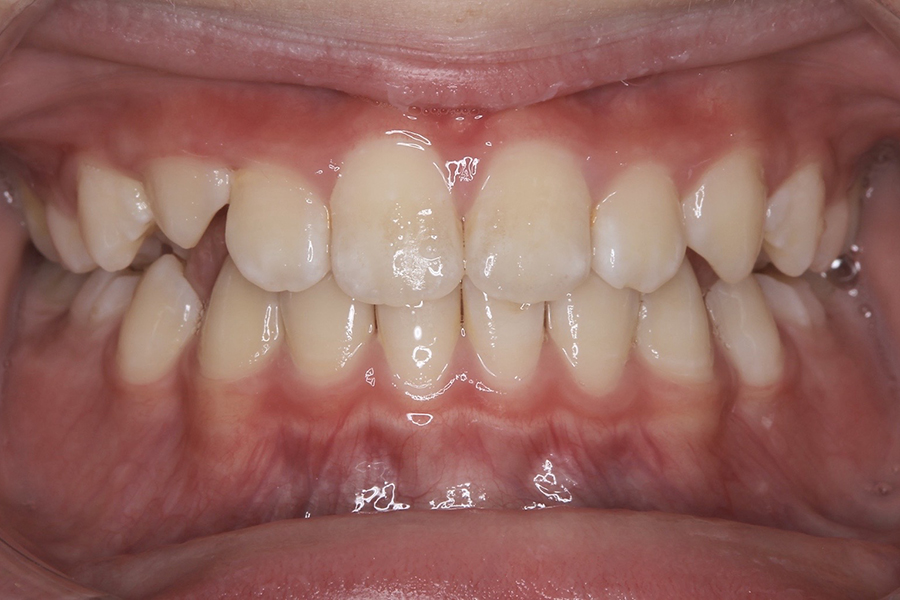

FDT症例② S.Hくん(10)

治療後

相談内容 |

うつ伏せ寝、口呼吸が気になる 歯並びの悪さ |

カウンセリング・診断結果 |

口呼吸、低位舌、上下顎劣成 |

行った治療内容 |

FDT(筋機能矯正治療/マイオブレース治療) |

治癒期間 |

2024.8.31〜 |

費用 |

385,000円(税込) |

治療リスクについて |

・お子様・保護者の協力が必要。 |

担当者からのコメント |

頑張り屋さんで真面目なHくん。正面から見ると一見綺麗ですが、横から見た時の前歯の出っ張りや永久歯の生えるスペースがないためFDTを始めました。 |